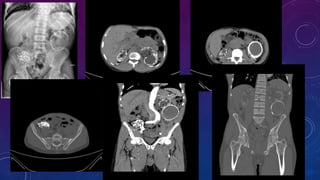

CT SCOUT RADIOGRAPHS

CYSTIC RENAL DISEASE

PRE TRANSPLANT

EVALUATION

• Failed kidney transplant

• Seminal vesicle / vas deferens calcification

FAILED BILATERAL RENAL TRANSPLANTS

CALCIFICATION

PRE RENAL TRANSPLANT EVALUATION.